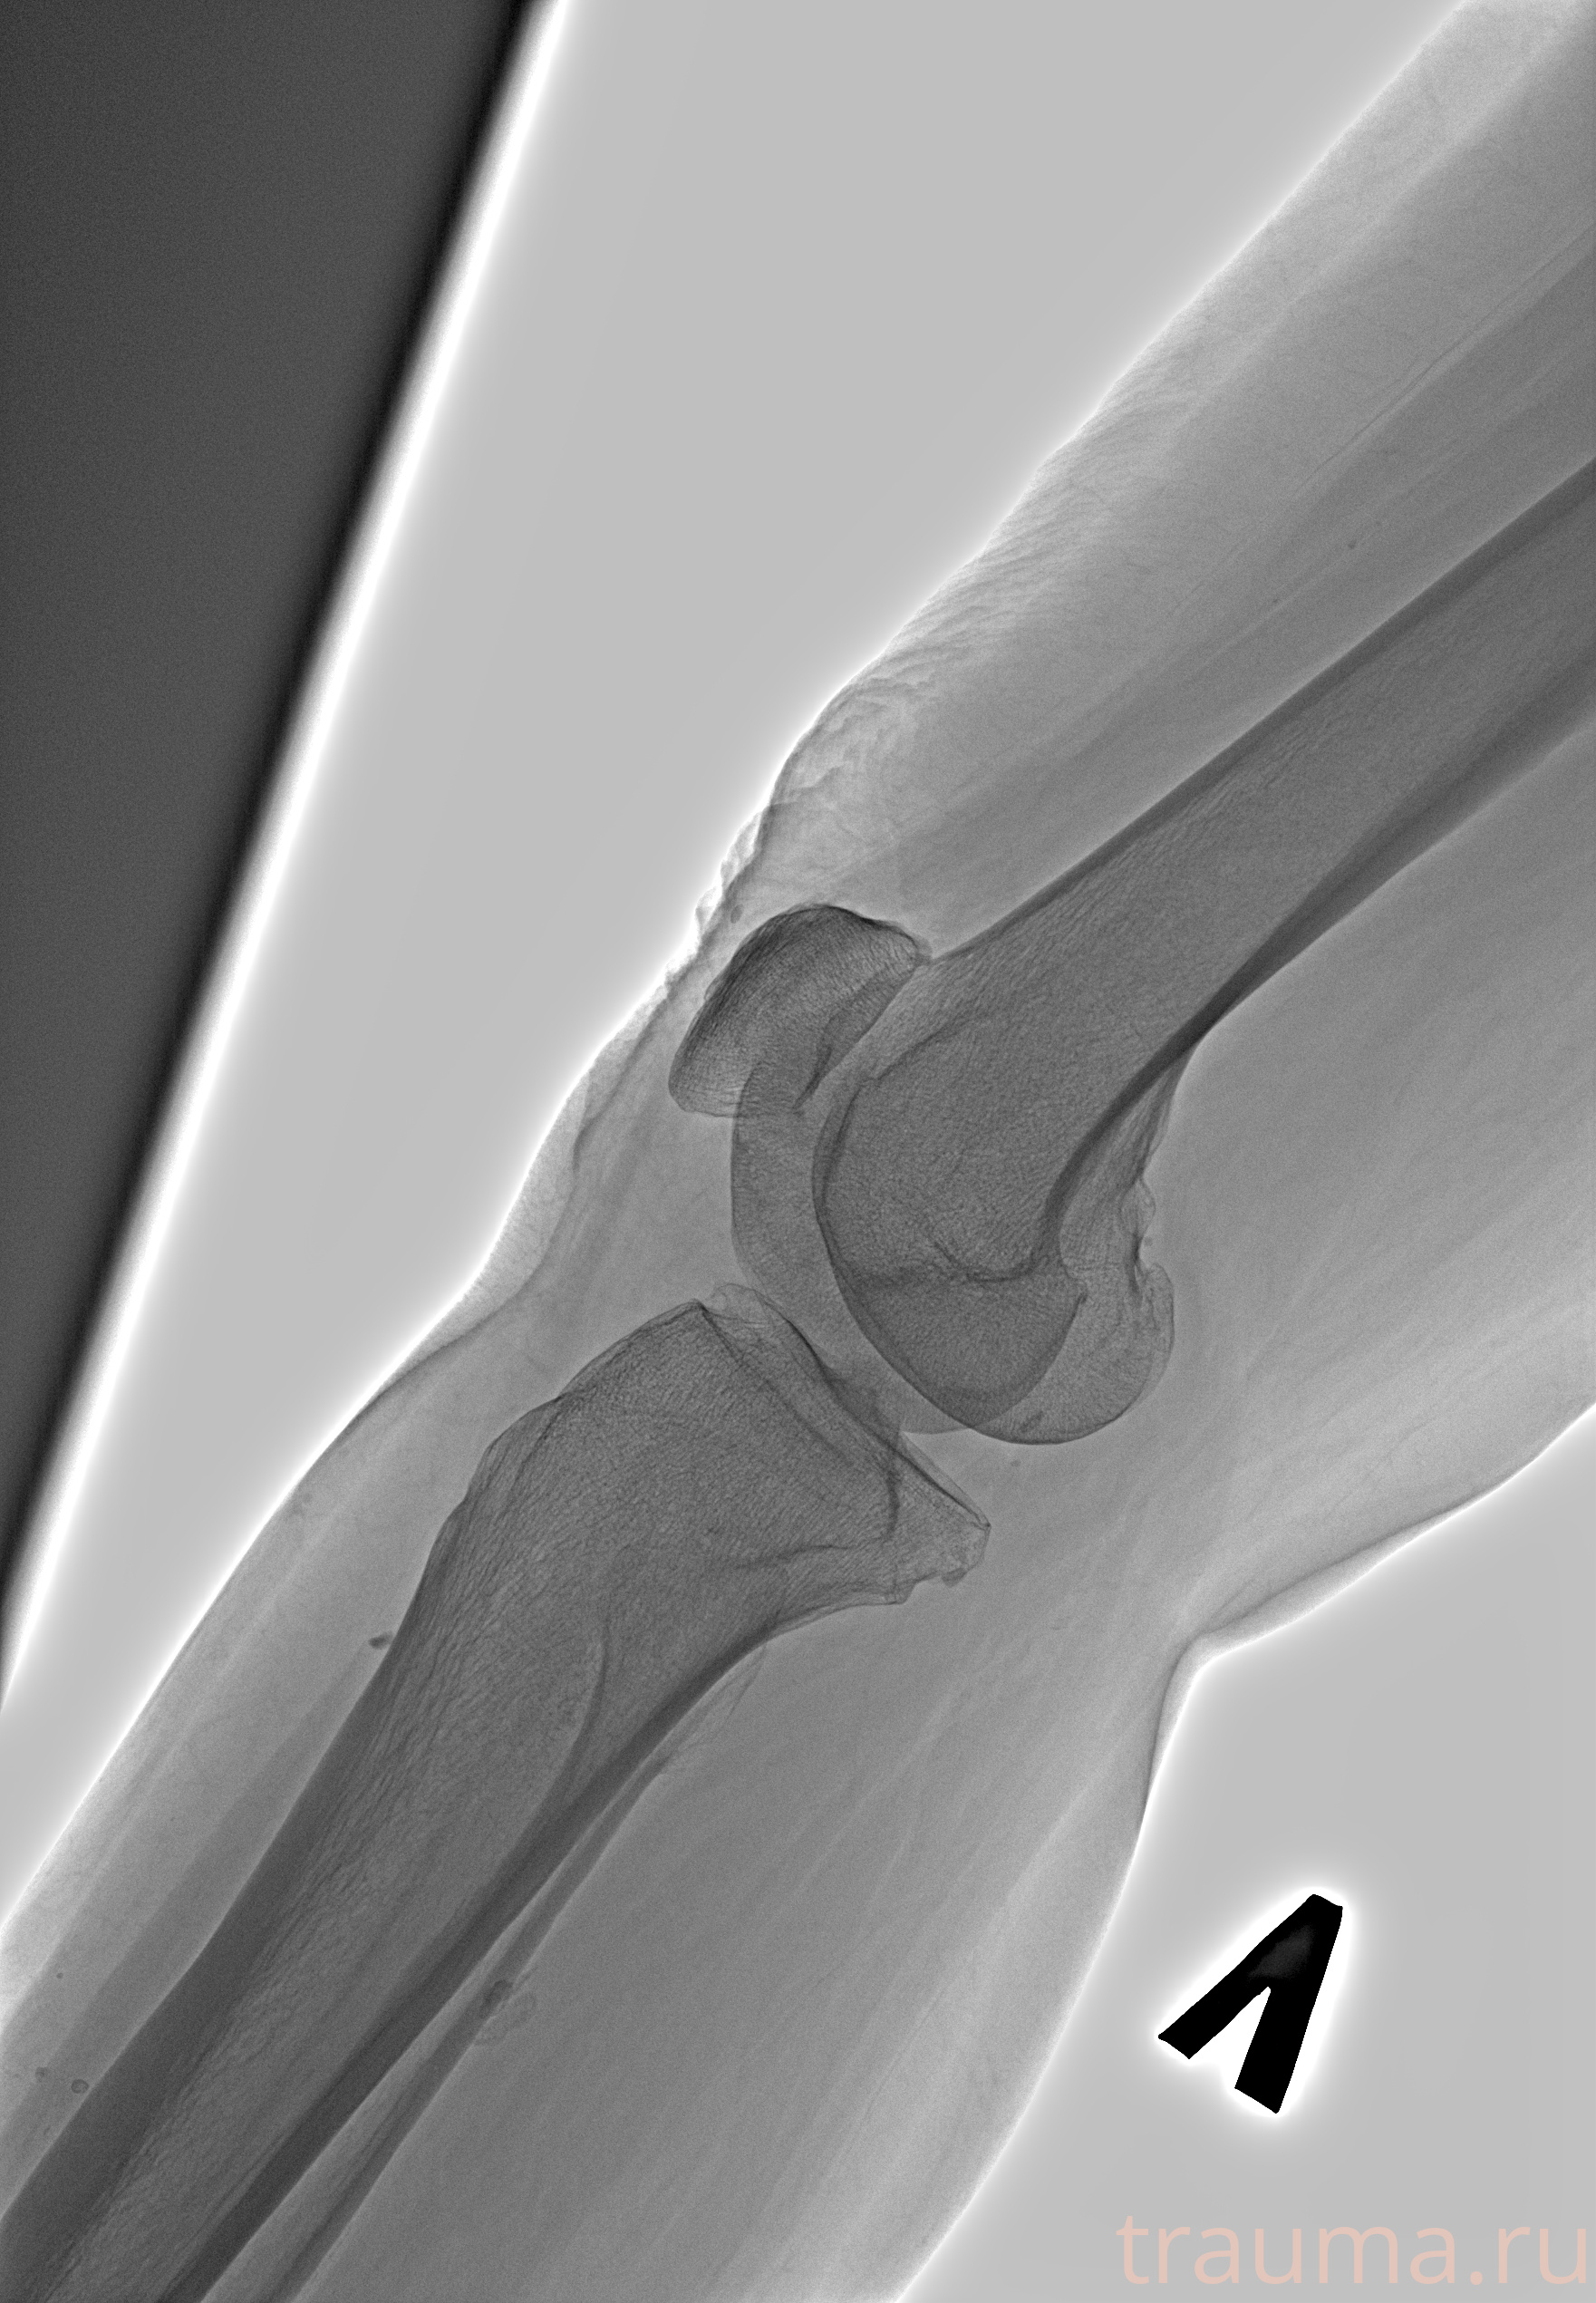

Рентген на дому: по вашему адресу приезжает врач-рентгенолог, травматолог-ортопед с мобильным рентгеновским аппаратом, проводит диагностику травмы или заболевания, делает необходимые рентгенограммы, дает рекомендации по дальнейшему лечению. Получить качественные снимки в домашних условиях возможно благодаря уникальной методике, разработанной МосРентген Центром для института  Склифосовского